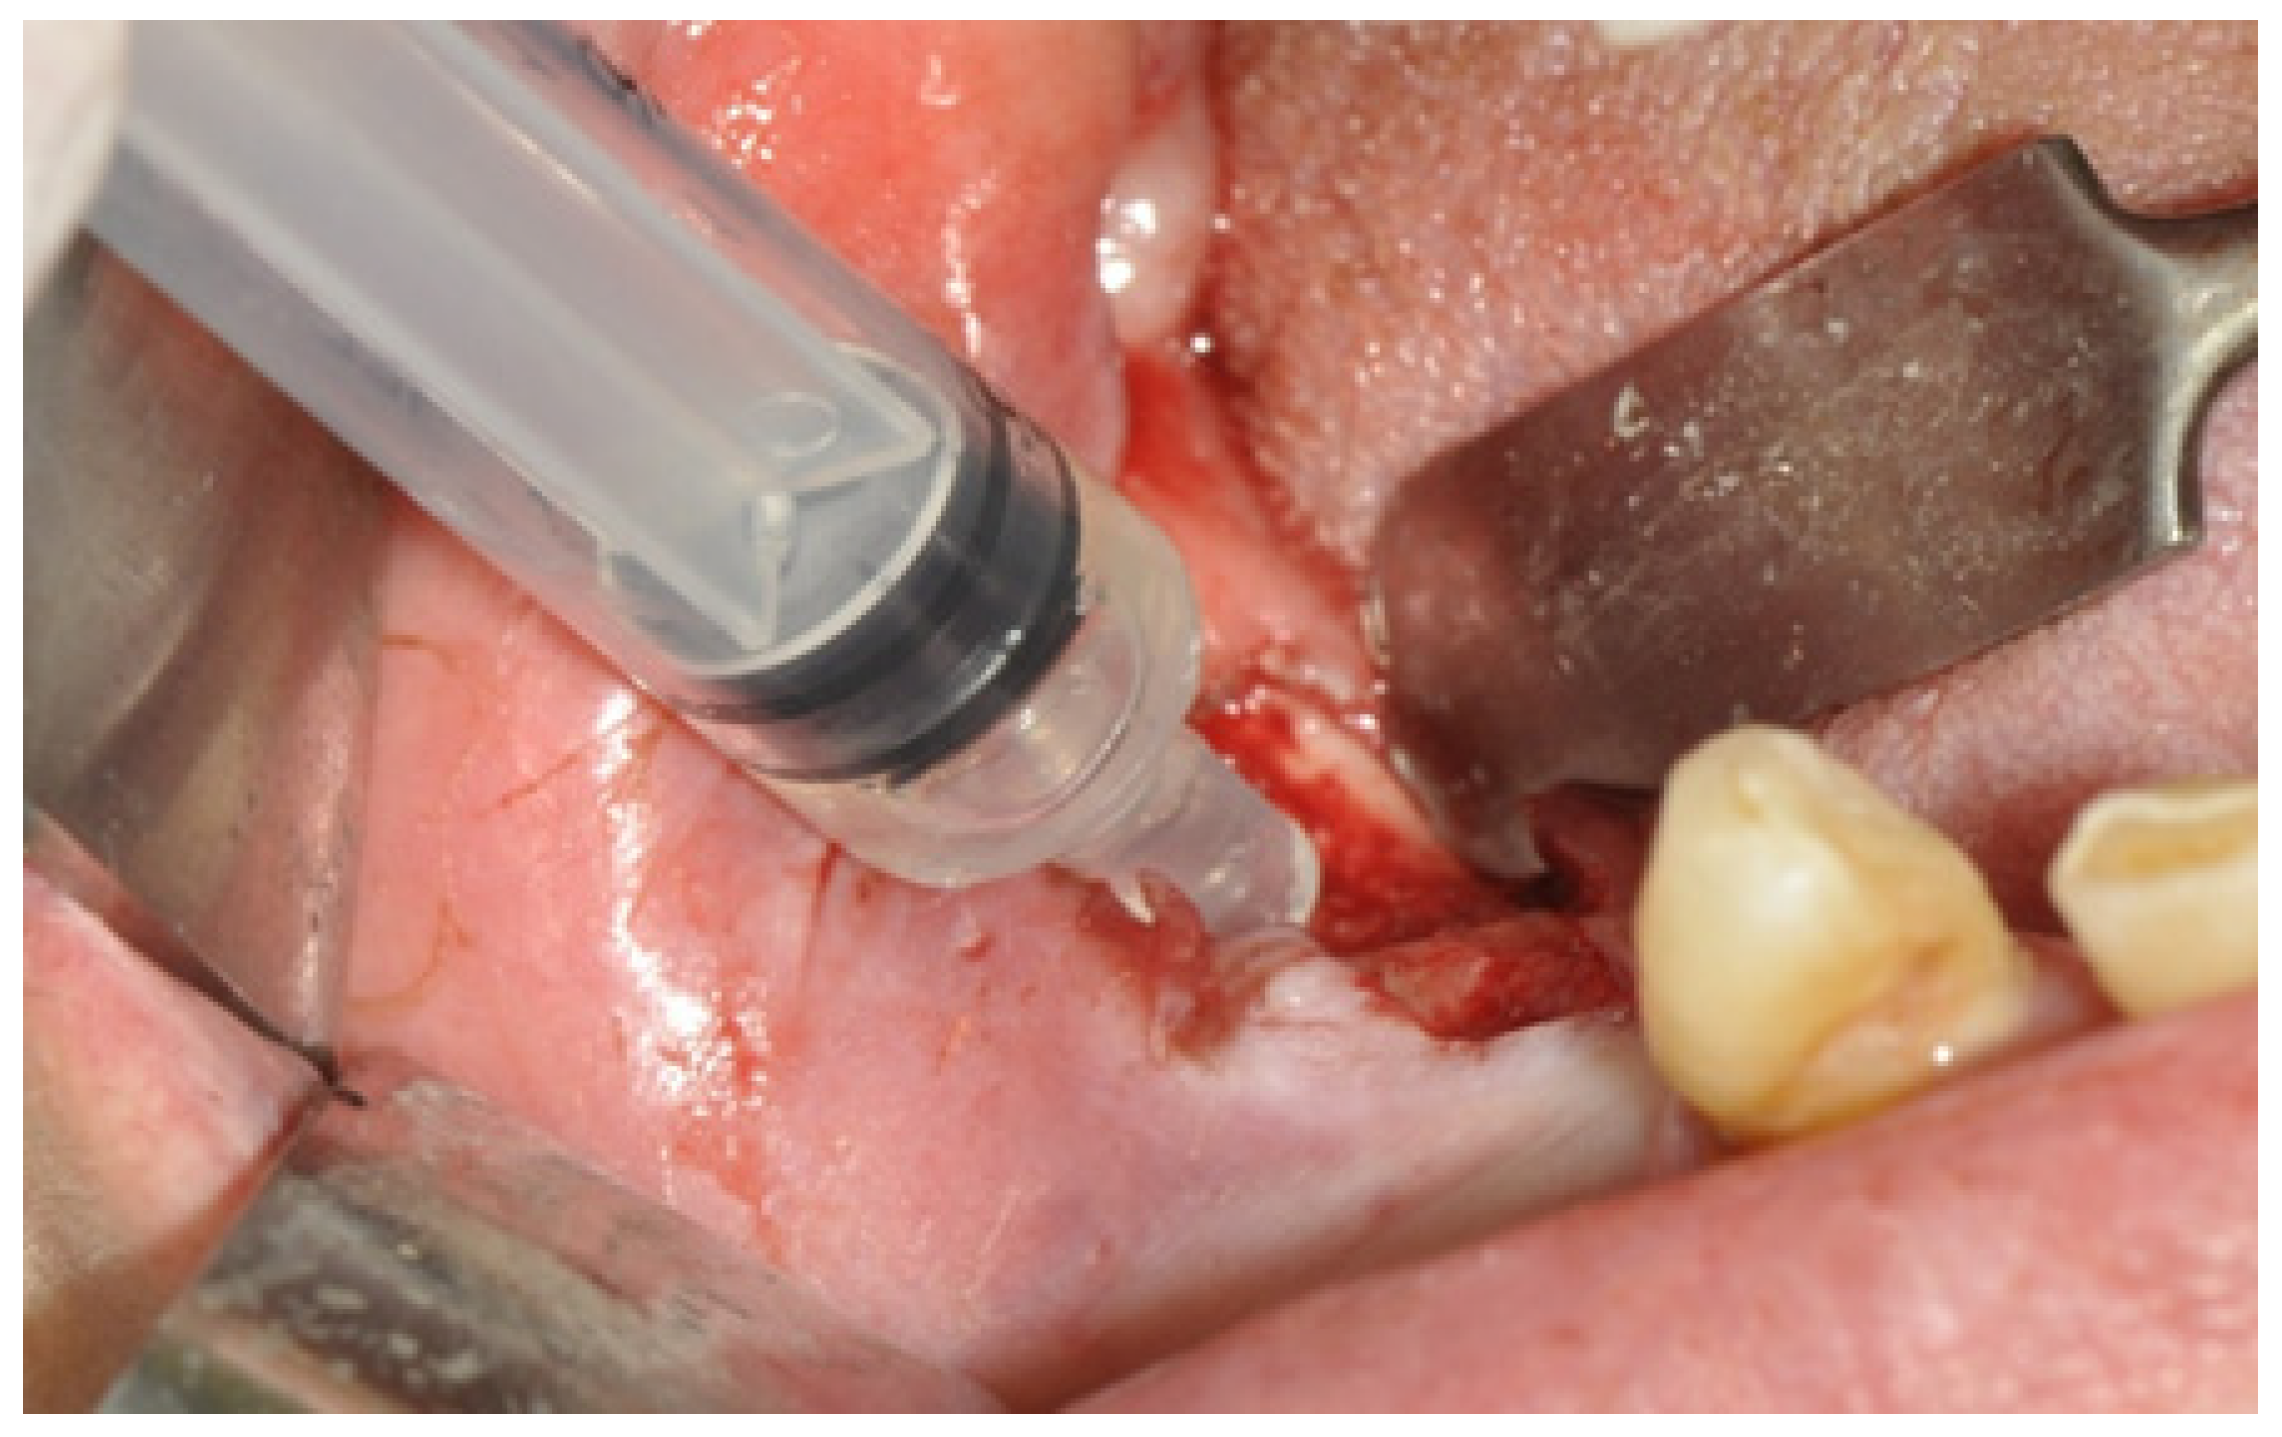

| Group 4 | 11 | MT + surgical treatment + laser Er:YAG |

| Group 5 | 7 | MT + ozone therapy + surgical treatment + laser Er:YAG. |